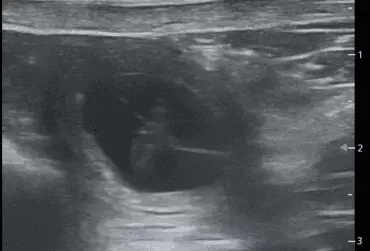

Żywy zarodek w jamie kosmówkowej w badaniu USG ciężarnej suki